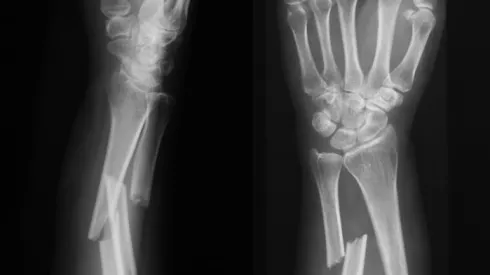

Biomateriał w strzykawce może przyśpieszyć zrastanie kości

Naukowiec pracuje nad biomateriałem z nanowłókien, który można wstrzykiwać bezpośrednio w miejsce złamania. Docelowo pomoże on pacjentom, których kości zrastają się zbyt wolno, lub kiedy proces ten utrudniają problemy związane m.in. z osteoporozą.